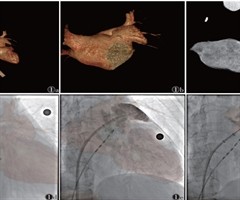

CT-DSA融合成像在左心耳封堵术中的应用

[摘要]目的:探讨CT-DSA融合成像在左心耳封堵术(LAAO)中应用的有效性和安全性。方法:收集110例行LAAO的患者,随机分为CT-DSA融合组(55例)和标准DSA组(55例)。CT-DSA融合组在CT-DSA融合图像引导下行LAA...